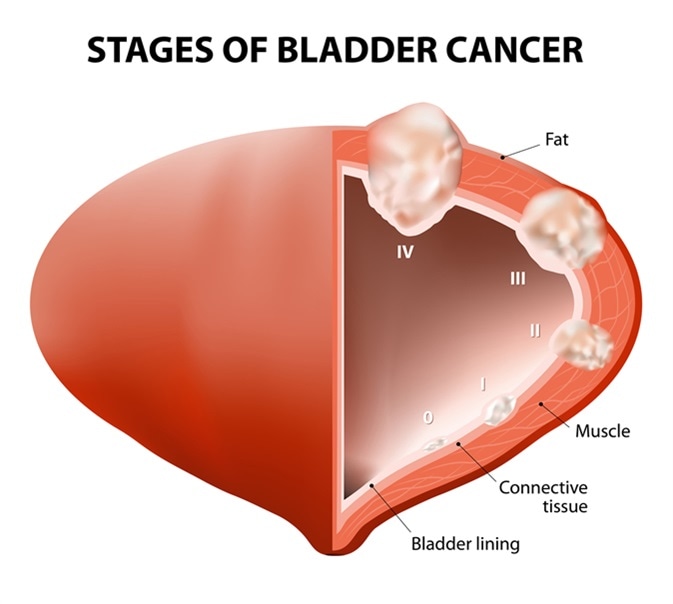

Illustration of different pathological stages of bladder cancer. Stage …

Stages of bladder cancer from Meyer et al., (2002). Bladder cancer can …

Overview of staging and grading of bladder cancer tumor. The figure was …

Bladder cancer stages stock illustration. Illustration of inside – 10332948